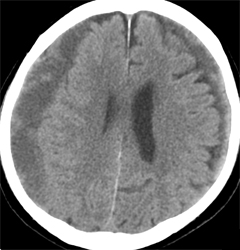

경막하 출혈의 진단은 환자의 신체검사와 함께 여러 가지 검사방법을 통해 이루어집니다.

- CT 또는 MRI 스캔 : 출혈량과 위치를 확인하기 위해 실시됩니다.

만성 경막하 출혈은 일반적으로 외상 후 3주 이상 경과한 출혈을 말하며, 치료는 다음과 같은 방법으로 이루어집니다:

- 관찰 치료 : 환자의 상태가 양호하고 출혈량이 적은 경우, 정기적으로 CT 검사를 통해 출혈량을 모니터링하며 경과를 지켜보는 방법도 사용됩니다.